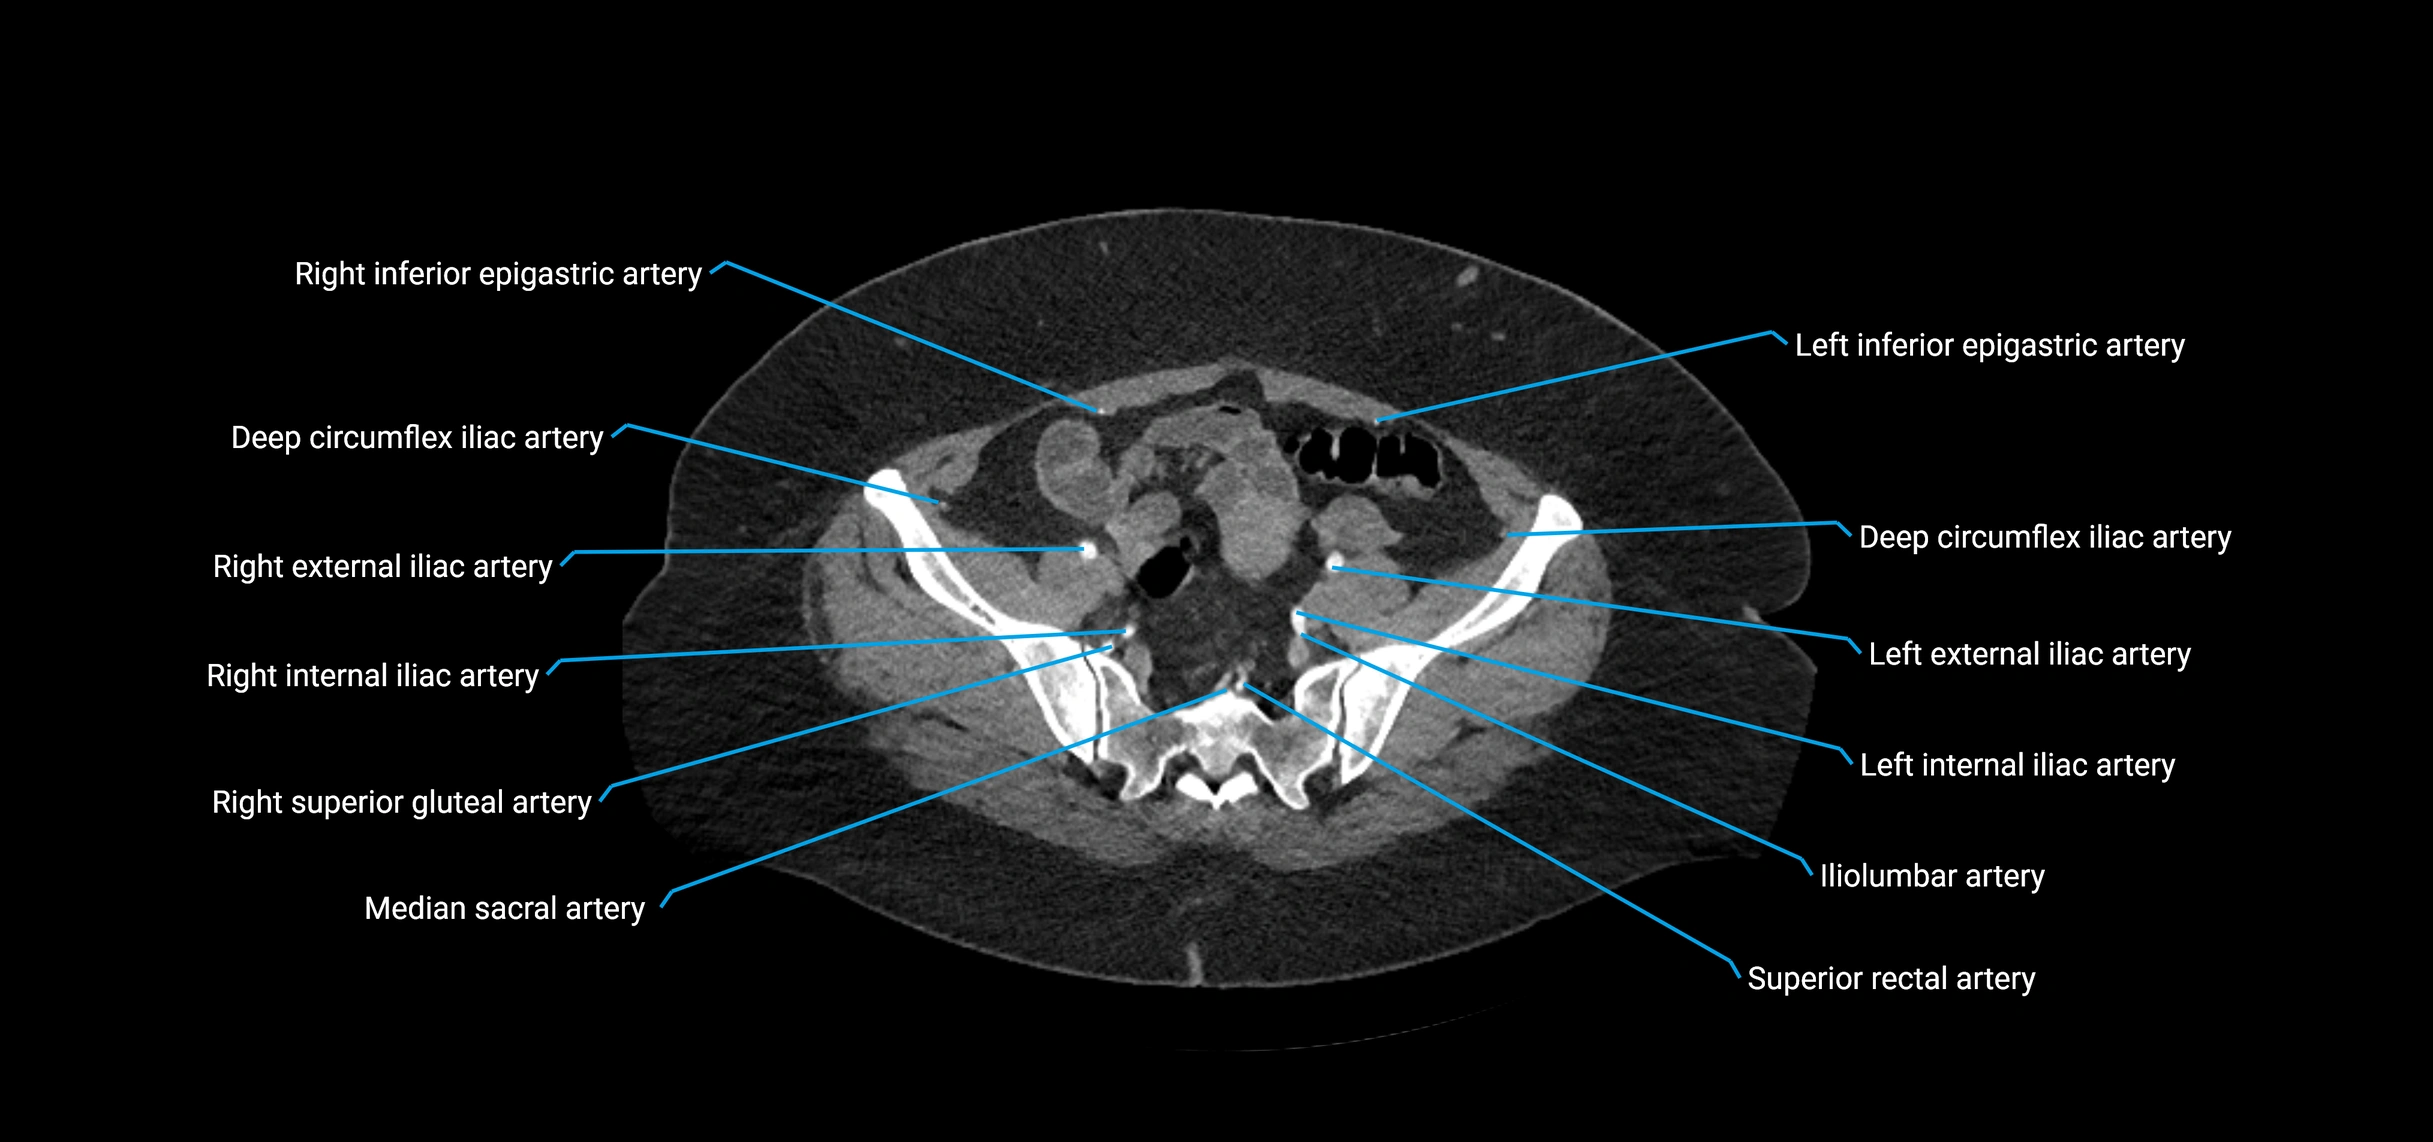

CT images

image

Contrast-enhanced CT (CTA):

• Gold standard for abdominal aortic imaging

• Provides excellent detail of lumen, wall, aneurysm, thrombus, and branch vessels

• Multiplanar and 3D reconstructions help in aneurysm measurement, stent graft planning, and dissection evaluation